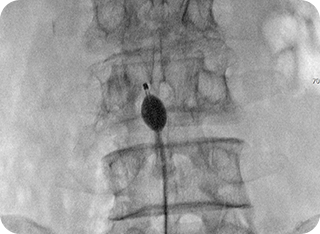

풍선확장술 사진1

풍선확장술 사진2

3

풍선확장술

미세한 풍선을 신경관이나 협착 부위에 삽입해 좁아진 공간을 확장시킨 뒤

약물을 투여합니다. 신경 압박을 줄이고 혈류를 개선하여 통증 완화와

기능 회복에 도움을 줍니다.

• #척추관협착증

• #허리디스크(추간판 탈출증)

• #수술 후 통증 증후군 등